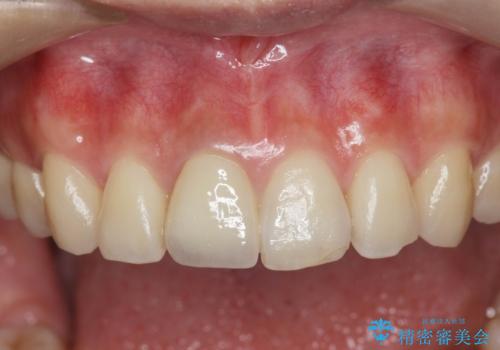

自然な色調をセラミッククラウンで再現することができ、審美性の改善に大変喜んでいただくことができました。